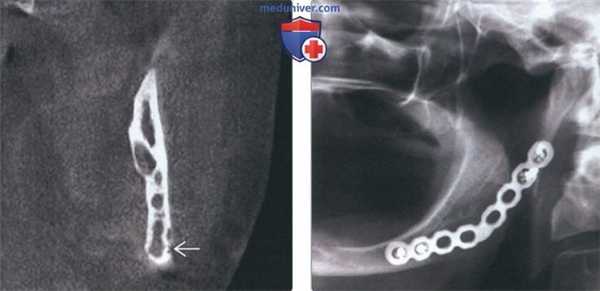

(Слева) На корональной КЛКТ у этого же пациента определяется многокамерное образование, не приводящее к вздутию. Не исключается эрозия щечной кортикальной пластинки в нижних отделах. При подозрении на вовлечение мягких тканей методом выбора является MPT.

(Справа) На панорамной рентгенограмме у этого же пациента, выполненной после операции, определяются признаки заживления кости с наличием стабилизирующей пластины. В случае таких агрессивных опухолей с целью недопущения рецидива рекомендуется резекция или широкое иссечение.

3. КТ при десмопластической фиброме челюсти:

• КЛКТ и КТ в костном окне:

о Позволяют лучше оценить многокамерную структуру, кортикальные эрозии, периостальную реакцию

4. Рекомендации по визуализации:

• Лучший метод визуализации:

о КЛКТ/КТ для оценки поражения кортикальной пластинки и периостальной реакции

о МРТ в случаях перфорации кортикальной пластинки:

- Для определения распространенности поражения мягких тканей